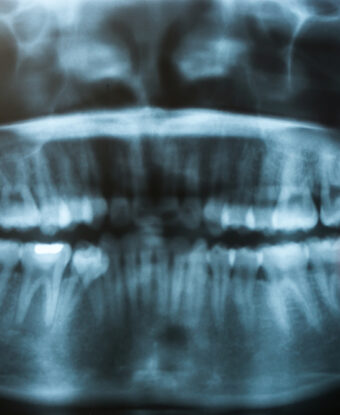

Gömülü yirmi yaş dişleri alt ve üst çenelerde ağızın en gerisinde bulunan ve yer darlığından dolayı normal süremeyen veya gelişemeyen dişlerdir.

Yirmi yaş dişi ağıza en son süren yetişkin dişleridir. İnsanlar genellikle sağ ve sol tarafta altta ve üstte olmak üzere toplamda 4 tane yirmi yaş dişe sahiptir.

Yirmi yaş dişleri genellikle 17-25 yaşları arasında bir zamanda sürerler. Bazı hastalarda yirmi yaş dişleri herhangi bir problem yaratmadan sürerek ikinci molar dişin hemen arkasında yerlerini alırlar. Ama çoğu vakada ağızda üçüncü molar dişlerin sürmesi için gerekli alan bulunmamaktadır. Bu yer darlığından dolayı yirmi yaş dişleri gömük kalabilir. Gömülü yirmi yaş dişleri kısmi olarak sürmüş olabilecekleri gibi tamamıyla da gömük olabilir